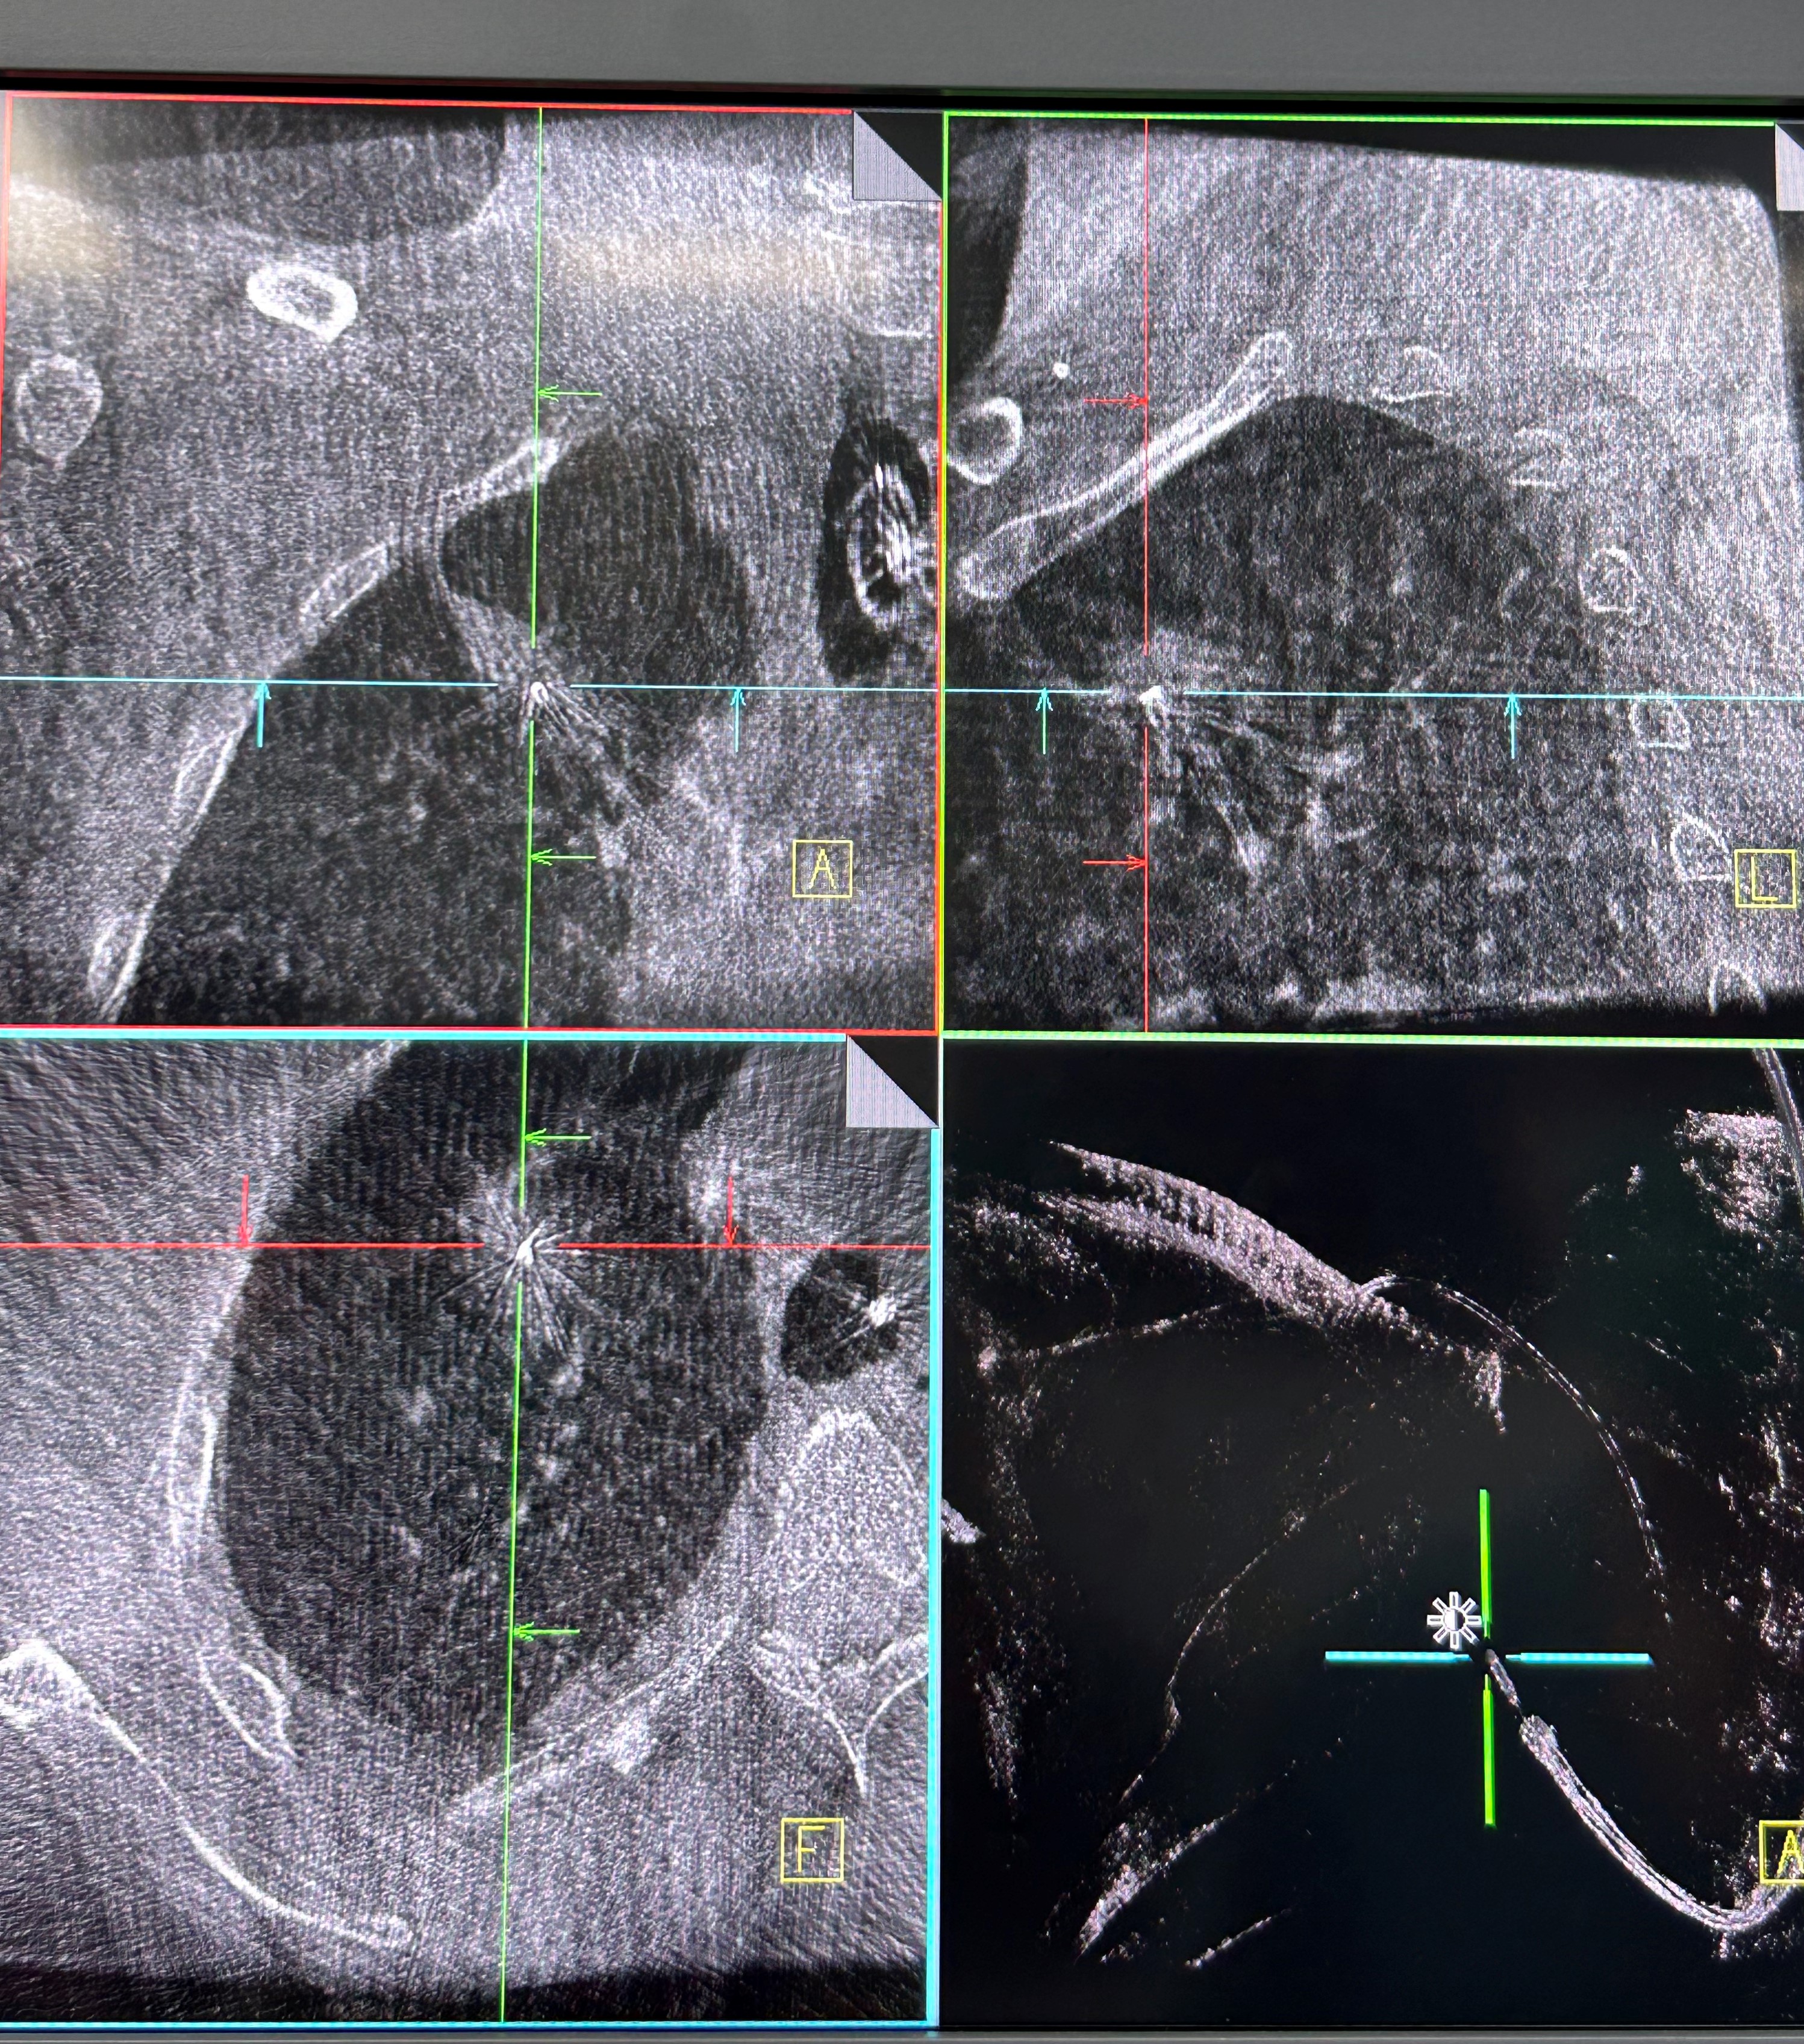

明确肿瘤诊断后,治疗方案即刻启动。团队经导航引导鞘管,精准插入一次性冷冻消融针(直径仅1.9mm)。再次通过CBCT确认消融针完全“扎根”于右上叶尖段病灶内后,开启冷冻治疗模式:以-160℃深低温冷冻10分钟、复温至45℃维持3分钟为一个治疗循环。完成了3次循环后,为确保病灶无遗漏,团队微调消融针位置,再次追加2次循环治疗。术后复查CBCT显示,病灶已呈现典型的冷冻后改变,术后两天复查胸部CT提示消融范围满意,治疗效果完全达到预期。整个手术过程中,患者生命体征始终平稳,术后第二天即可下床活动,真正实现了“微创治疗、快速恢复”的目标。

治疗后